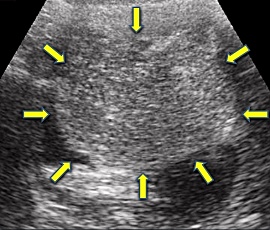

急性腹症にて救急受診。腹部超音波検査にて骨盤内に子宮、膀胱を圧排する約15cm大の辺縁が円滑な単房性腫瘤(矢印)を認め、精査の結果、卵巣腫瘍(矢印)と診断。手術を施行した。病理結果は、成熟嚢胞性奇形腫であった。

超音波画像